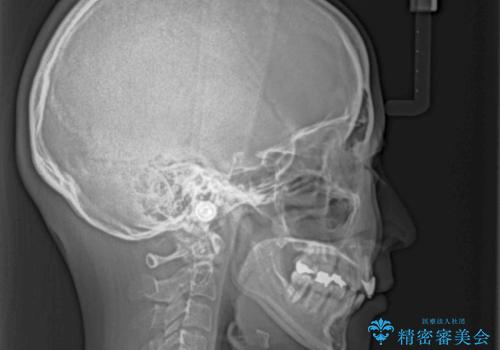

横から見た際の口元の飛び出した印象も改善したいとのことで、上下左右の第一小臼歯4本を抜歯し、ワイヤー装置にて抜歯矯正を行うこととしました。

順調に歯が動き、補綴治療も含め2年弱で治療を終えることができました。